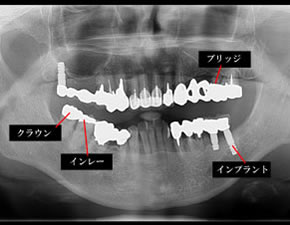

※当院では、初診時に全額の画像診察をおこないます。

//一般歯科//

//インプラント//

//審美歯科//